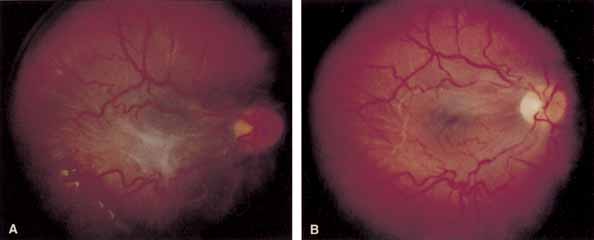

Some authors have commented on the importance of a posterior vitreous detachment in the pathogenesis of a macular hole.34,35 It is difficult to determine the vitreoretinal relationship preoperatively, even with careful slit-lamp evaluation. OCT testing can sometimes be helpful. However, the vitreomacular relationships are more accurately determined intraoperatively with use of oblique intraocular illumination and by noting the effect of gentle tractional forces on the macula during the vitrectomy. In some cases, what was thought to be a posterior vitreous separation preoperatively was actually found to be a large, optically empty space (Fig. 3).

Tissue surgically peeled from the macular region in cases of impending macular hole has been found to be clinically consistent with posterior hyaloid. This finding was supported by electron microscopic examination of the tissue (Fig. 4).13,36 This observation is supported by the work of Kishi and Shimizu.37 They noted a large, optically empty space that appeared to be a complete posterior vitreous detachment in eyes with advanced liquefaction of the vitreous. They termed this area the posterior precortical vitreous pocket (PPVP). They found this pocket in 48 of 84 eyes with either an incomplete or no posterior vitreous detachment, and in 19 of 36 eyes with a posterior vitreous detachment. They noted that in eyes with advanced liquefaction of the vitreous, a large PPVP appeared to be a complete posterior vitreous detachment. In all of their postmortem cases, the posterior layer of the PPVP was found to be a thin layer of cortical vitreous. The presence of this PPVP strengthens the hypothesis that contraction of remaining attached cortical vitreous causes tangential traction on the macula, which gives the clinical appearance of an idiopathic macular cyst or hole.13,25,26,38 These impending holes or cysts' have been noted to resolve with spontaneous or surgical stripping of the membranes.13,25